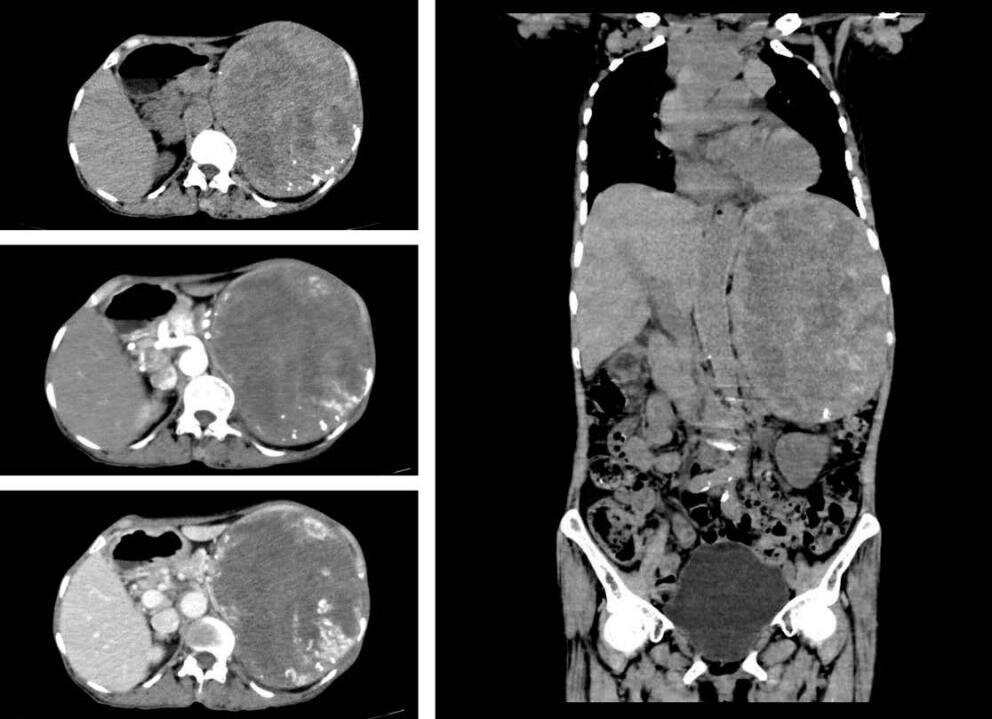

林伯的肿瘤不仅“恶性”、“晚期”,而且“巨大”,表面皮肤已大面积受侵犯、破溃流脓。

医院耳鼻咽喉头颈外科手术团队充分考虑和评估手术风险、病情严重性,以及患者术后容貌的修复,焦粤农、谭国杰等医生针对治疗方案反复讨论,最终决定为患者实施腮腺肿瘤切除术,并运用胸锁乳突肌皮瓣移植这项新技术。

手术中,团队准确把握面神经各分支的走行及解剖的特点以及与邻近组织的关系,安全地解剖和分离面神经,成功将瘤体完整剥离切除,并在患者胸前取一大小合适的皮瓣,为患者行胸锁乳突肌皮瓣移植,填补了腮腺肿瘤切除形成的凹陷,为患者修复容颜,顺利完成手术。